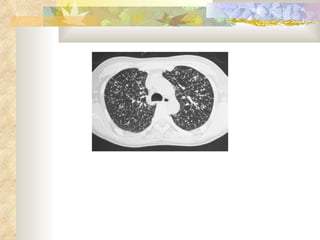

Miliary tuberculosis in an infant whose uncle also had tuberculosis. There is adenopathy in addition to the millet seed–like lesions

Miliary tuberculosis inan infant whose uncle also had tuberculosis. There is adenopathy in addition to the millet seed–like lesions